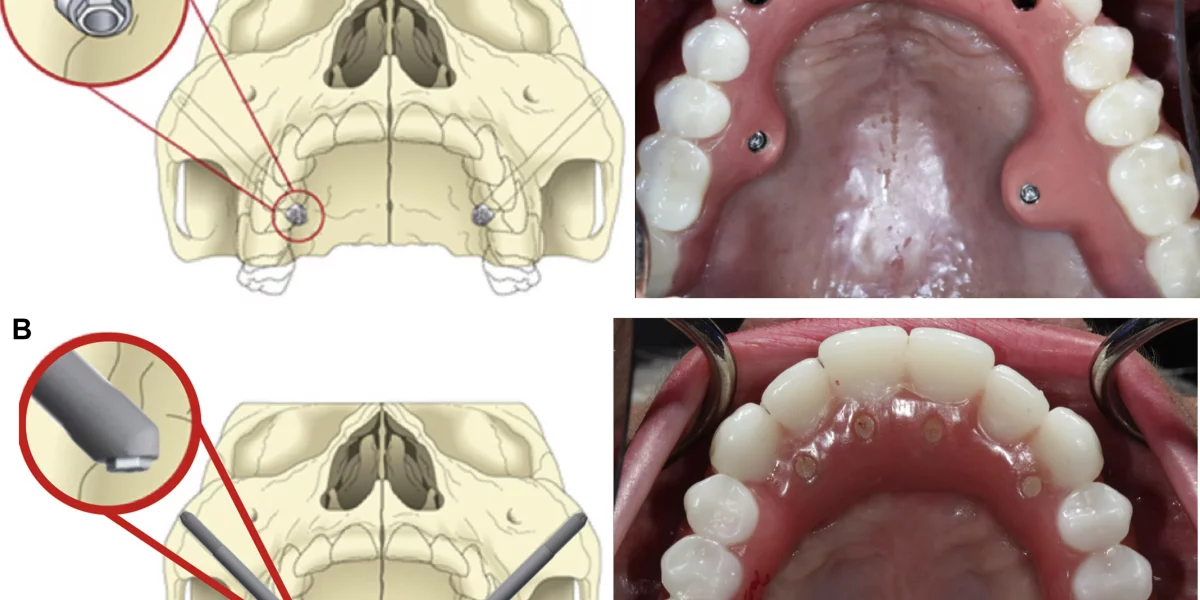

顳顎植體是什麼?

與傳統植體固定在上顎骨不同,顳顎植體較長,並放置在顳骨(臉頰骨)中。這個區域即使上顎經歷了大量的吸收仍然通常保持致密健康。這就是為什麼這種技術非常適合有嚴重上顎骨流失的患者,他們被告知沒有進行大規模骨移植的情況下,植體是不可行的。